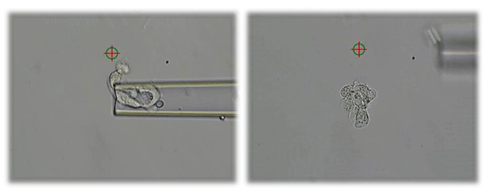

Selve biopsi-tagningen foregår ved at skyde et lille hul i embryonets skal. Herigennem suger vi trophectodermceller ud og op i en tynd pipette. Med laseren kan vi adskille de udtagne celler fra resten af de tilbageblevne trophectodermceller.

Med laser skydes der et hul i æggets skal og ved hjælp af pipetten suges celler ud Disse adskilles fra de resterende trophectodermceller ved hjælp af laseren.

Her ses en biopsi, der består af cirka 7 celler i pipetten. Når cellerne er adskilt fra blastocysten, bliver de overført til en anden bakke, hvor de vaskes, lynfryses og sendes til analyse.

De udtagne celler lynfryses og sendes til analyse på Molekylær Diagnostisk Afsnit. Her udføres den analyse, der afgør, om embryonet er sygt eller raskt.

Embryonet kommer sig hurtigt efter biopsi-tagningen og er klar til at blive frosset ned ganske kort tid efter biopsien.